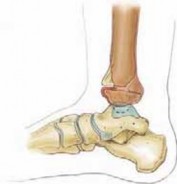

MEDIAL MALLEOLAR FRACTURES: SALTER-HARRIS TYPE III AND IV FRACTURES

1. If there is only a small metaphyseal fragment, these fractures may be fixed with 4.0-mm cancellous bone screws or Kirschner wires completely within the epiphysis and parallel to the physis and joint (

TECH FIG 4

).

1. These fractures can be treated percutaneously if anatomic reduction can be attained by closed treatment; however, a small incision can easily allow direct visualization of the reduction. A BTECH FIG 4 • Medial malleolar fracture fixation with an epiphyseal screw. If there is only a small metaphyseal fragment, medial malleolar fractures can be fixed with compressive screws placed within the epiphysis, parallel to the physis. Cannulated screws can be used to help ensure the physis is not compromised. 23. If a larger metaphyseal fragment is present, another metaphyseal screw can be placed parallel to the physis in addition to the epiphyseal screw.